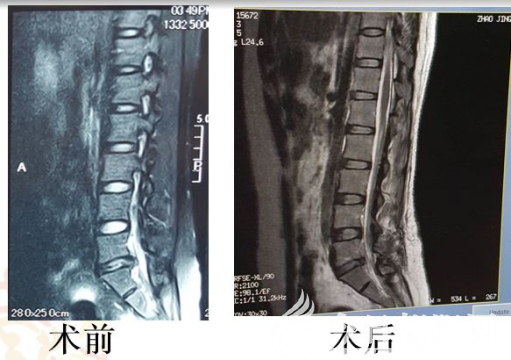

患者趙某,39歲,女性,受腰間盤突出癥困擾十余年,每年發(fā)作數(shù)次。發(fā)作時(shí),腰痛向右下肢放射,不能行走。此次入院前兩周發(fā)病,臥床休息后不能緩解,需強(qiáng)迫胸膝位,磁共振顯示:腰5骶1椎間盤突出,繼發(fā)椎管狹窄。

患者經(jīng)多方咨詢,找到該院神經(jīng)外二科張文主任和范廣明副主任醫(yī)師求醫(yī)??紤]患者正值青壯年,間盤突出為單節(jié)段,不存在脊柱不穩(wěn),不需內(nèi)固定。經(jīng)過(guò)研究,患者及家屬欣然接受微創(chuàng)的椎間隙開(kāi)窗顯微鏡下髓核摘除神經(jīng)減壓術(shù)。手術(shù)過(guò)程順利,術(shù)后患者右下肢能抬高60°,腰腿痛癥狀完全消失,術(shù)后3天下地行走,術(shù)后6天笑著出院,為該院再添新的光彩。